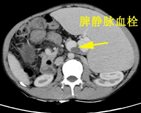

患者朱XX,男,49岁,因“上腹部胀痛2天”2015年入院,查体:脾脏肋下15cm。入院时血液学检查:白细胞明显降低仅为0.8X109/L,血小板明显降低仅为 23X109/L。入院时彩超:脾大Ⅲ度,门静脉、脾静脉内异常回声(考虑血栓形成),腹腔积液。

入院CT

临床诊断:肝硬化、门静脉高压 门静脉、脾静脉血栓 脾功能亢进 食管、胃底静脉曲张(重度)门脉高压性胃病